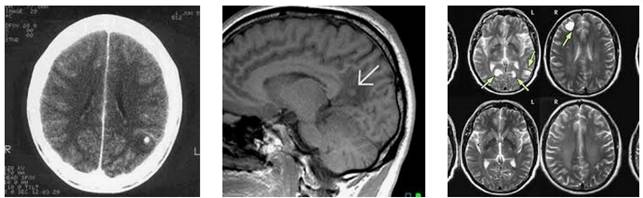

Hình 7

Hình 8